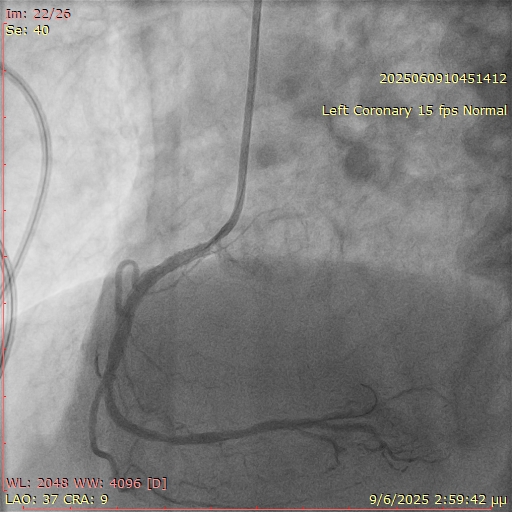

A 67-year-old man with a history of coronary artery disease and prior percutaneous coronary interventions (PCI) of the left anterior descending artery and the right coronary artery (RCA) presented with stable angina. During diagnostic coronary angiography, selective engagement of the RCA using a 5F Judkins right (JR) 4 catheter proved challenging (Figure 1). However, angiographic signs suggested significant restenosis at the ostium and proximal RCA. PCI was initiated using a 6F JR 4 guiding catheter; operators employed the "floating wire" technique, maintaining the wire at the catheter tip until ostial engagement was achieved. After several attempts, the wire was successfully advanced distally into the RCA.